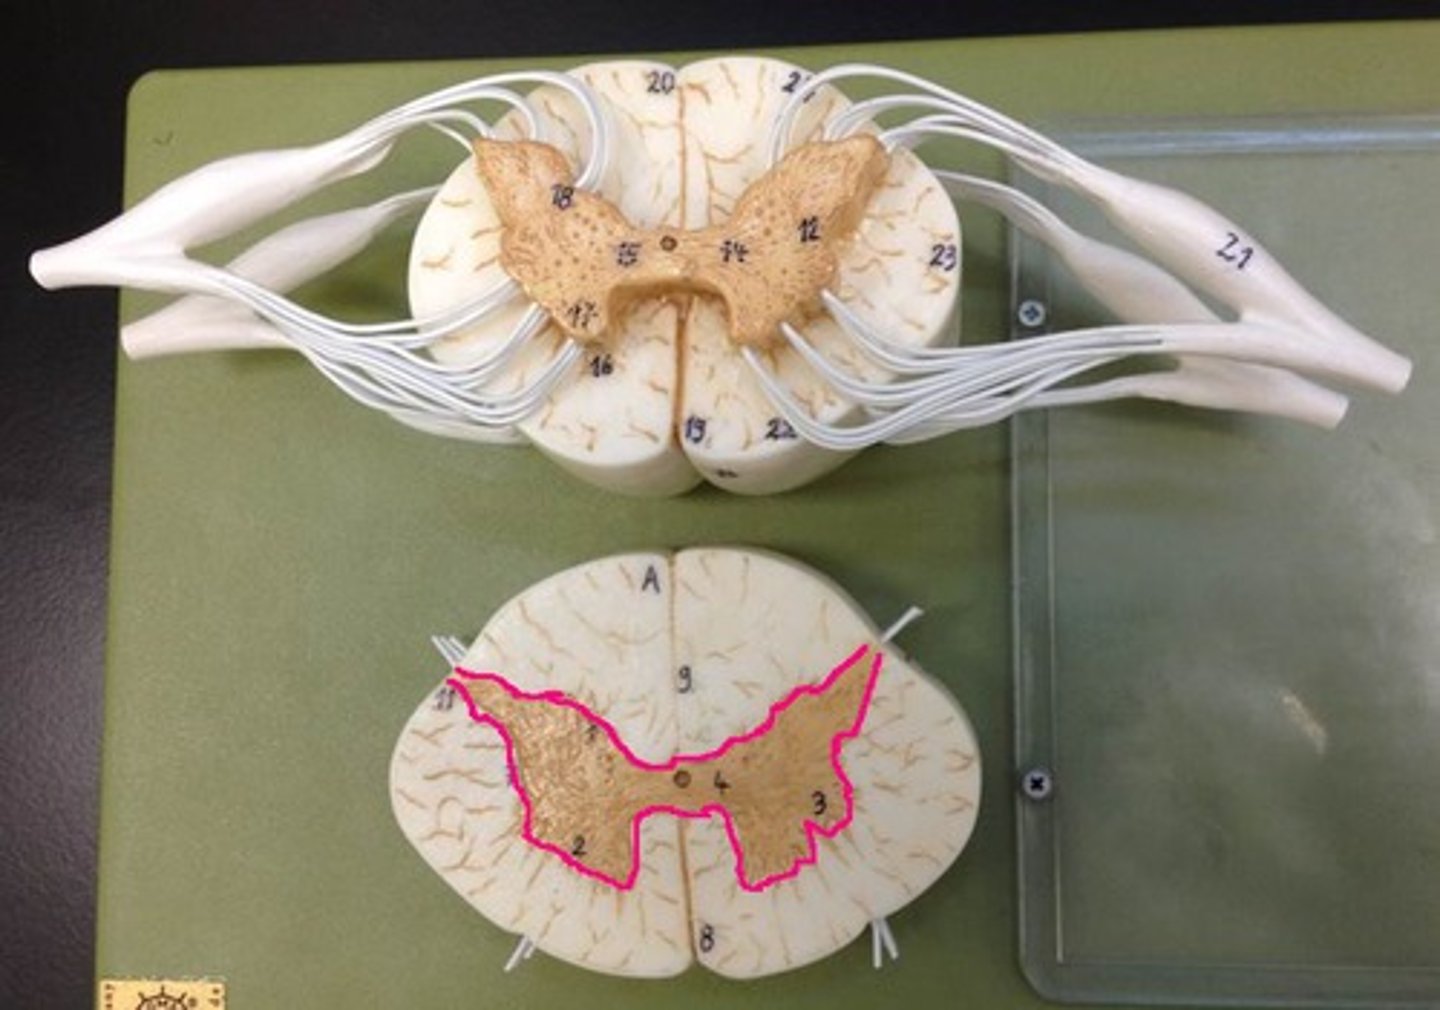

Gray matter

Posterior horn

Anterior horn

Lateral horn

G

Gray commissure

gray matter around this structure

Central canal

White matter

Posterior funiculus

Green

Anterior funiculus

Yellow

Lateral funiculus

Red

Posterior median sulcus

green

Anterior median fissure

red